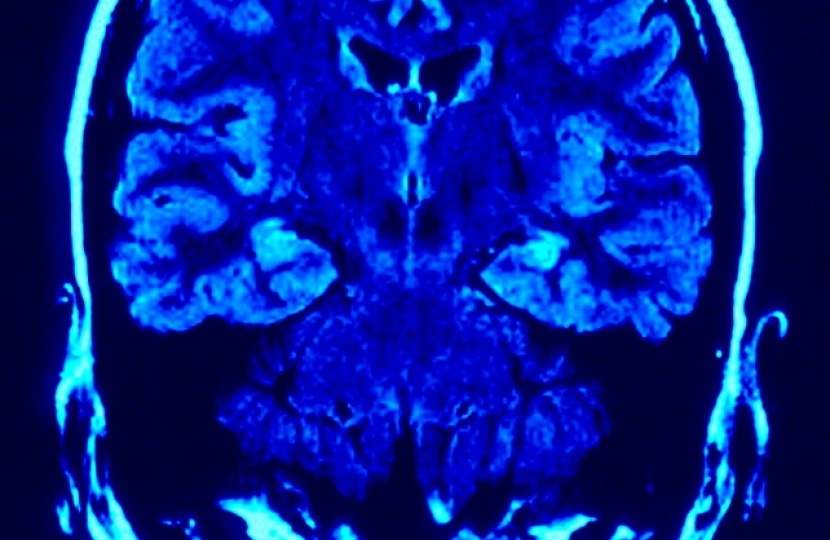

Mr Isherwood, who Chairs the Cross Party Group on Neurological Conditions, noted that epilepsy is the most common serious neurological condition and that epilepsy-related episodes are the commonest reason for emergency health service activity, accounting for the largest number of bed days in our district general hospitals.